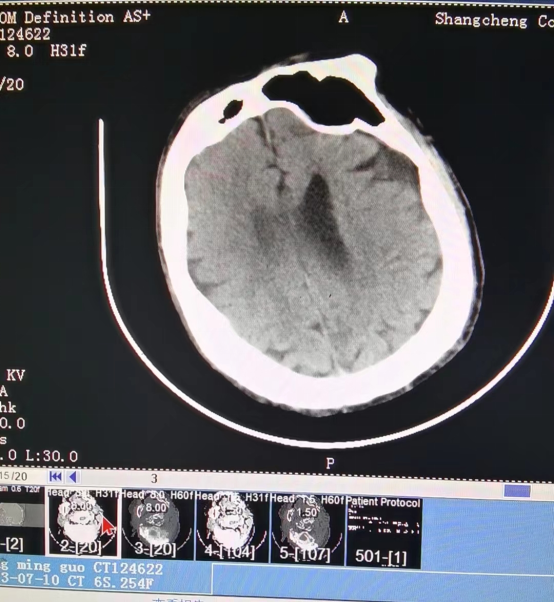

近日,55岁的冯先生突发急性脑梗死,我院卒中中心启动绿色通道,给予静脉溶栓桥接取栓治疗,成功打通堵塞的“生命管道”,患者转危为安,术后恢复良好,避免了“一人中风,全家瘫痪”的悲剧。

冯先生的成功救治,是静脉溶栓桥接动脉取栓治疗的完美结合。这次抢救工作的完美收官依靠的绝不仅仅是个人能力,它是整个团队共同努力的结果,检验了我院卒中中心对于脑卒中患者的快速鉴别诊断及多学科协作救治能力。我院卒中中心就是这样一支这样技术精湛、素质过硬的团队,在卒中介入治疗领域已经具备较强的综合实力,他们始终秉持着时间就是大脑、时间就是生命的理念,不断优化卒中急救模式和流程,为保障大别山区卒中患者能够得到及时、规范、有效的救治,降低县域卒中死亡率、致残率而不懈努力,为助力全面建设健康中国贡献自己的力量。